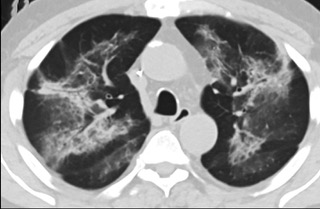

![6AYɨCTfʹ_ܤ]nt]QacT(ïfCT_)](./W020210804330783277896.jpeg)

ݐ6AYɨCTfʹ_ܤ]nt]QacT(ïfCT_)

![6AYɨCTfʹ_ܤ]nt]QacT(ïfCT_)](./W020210804330783485235.jpeg)